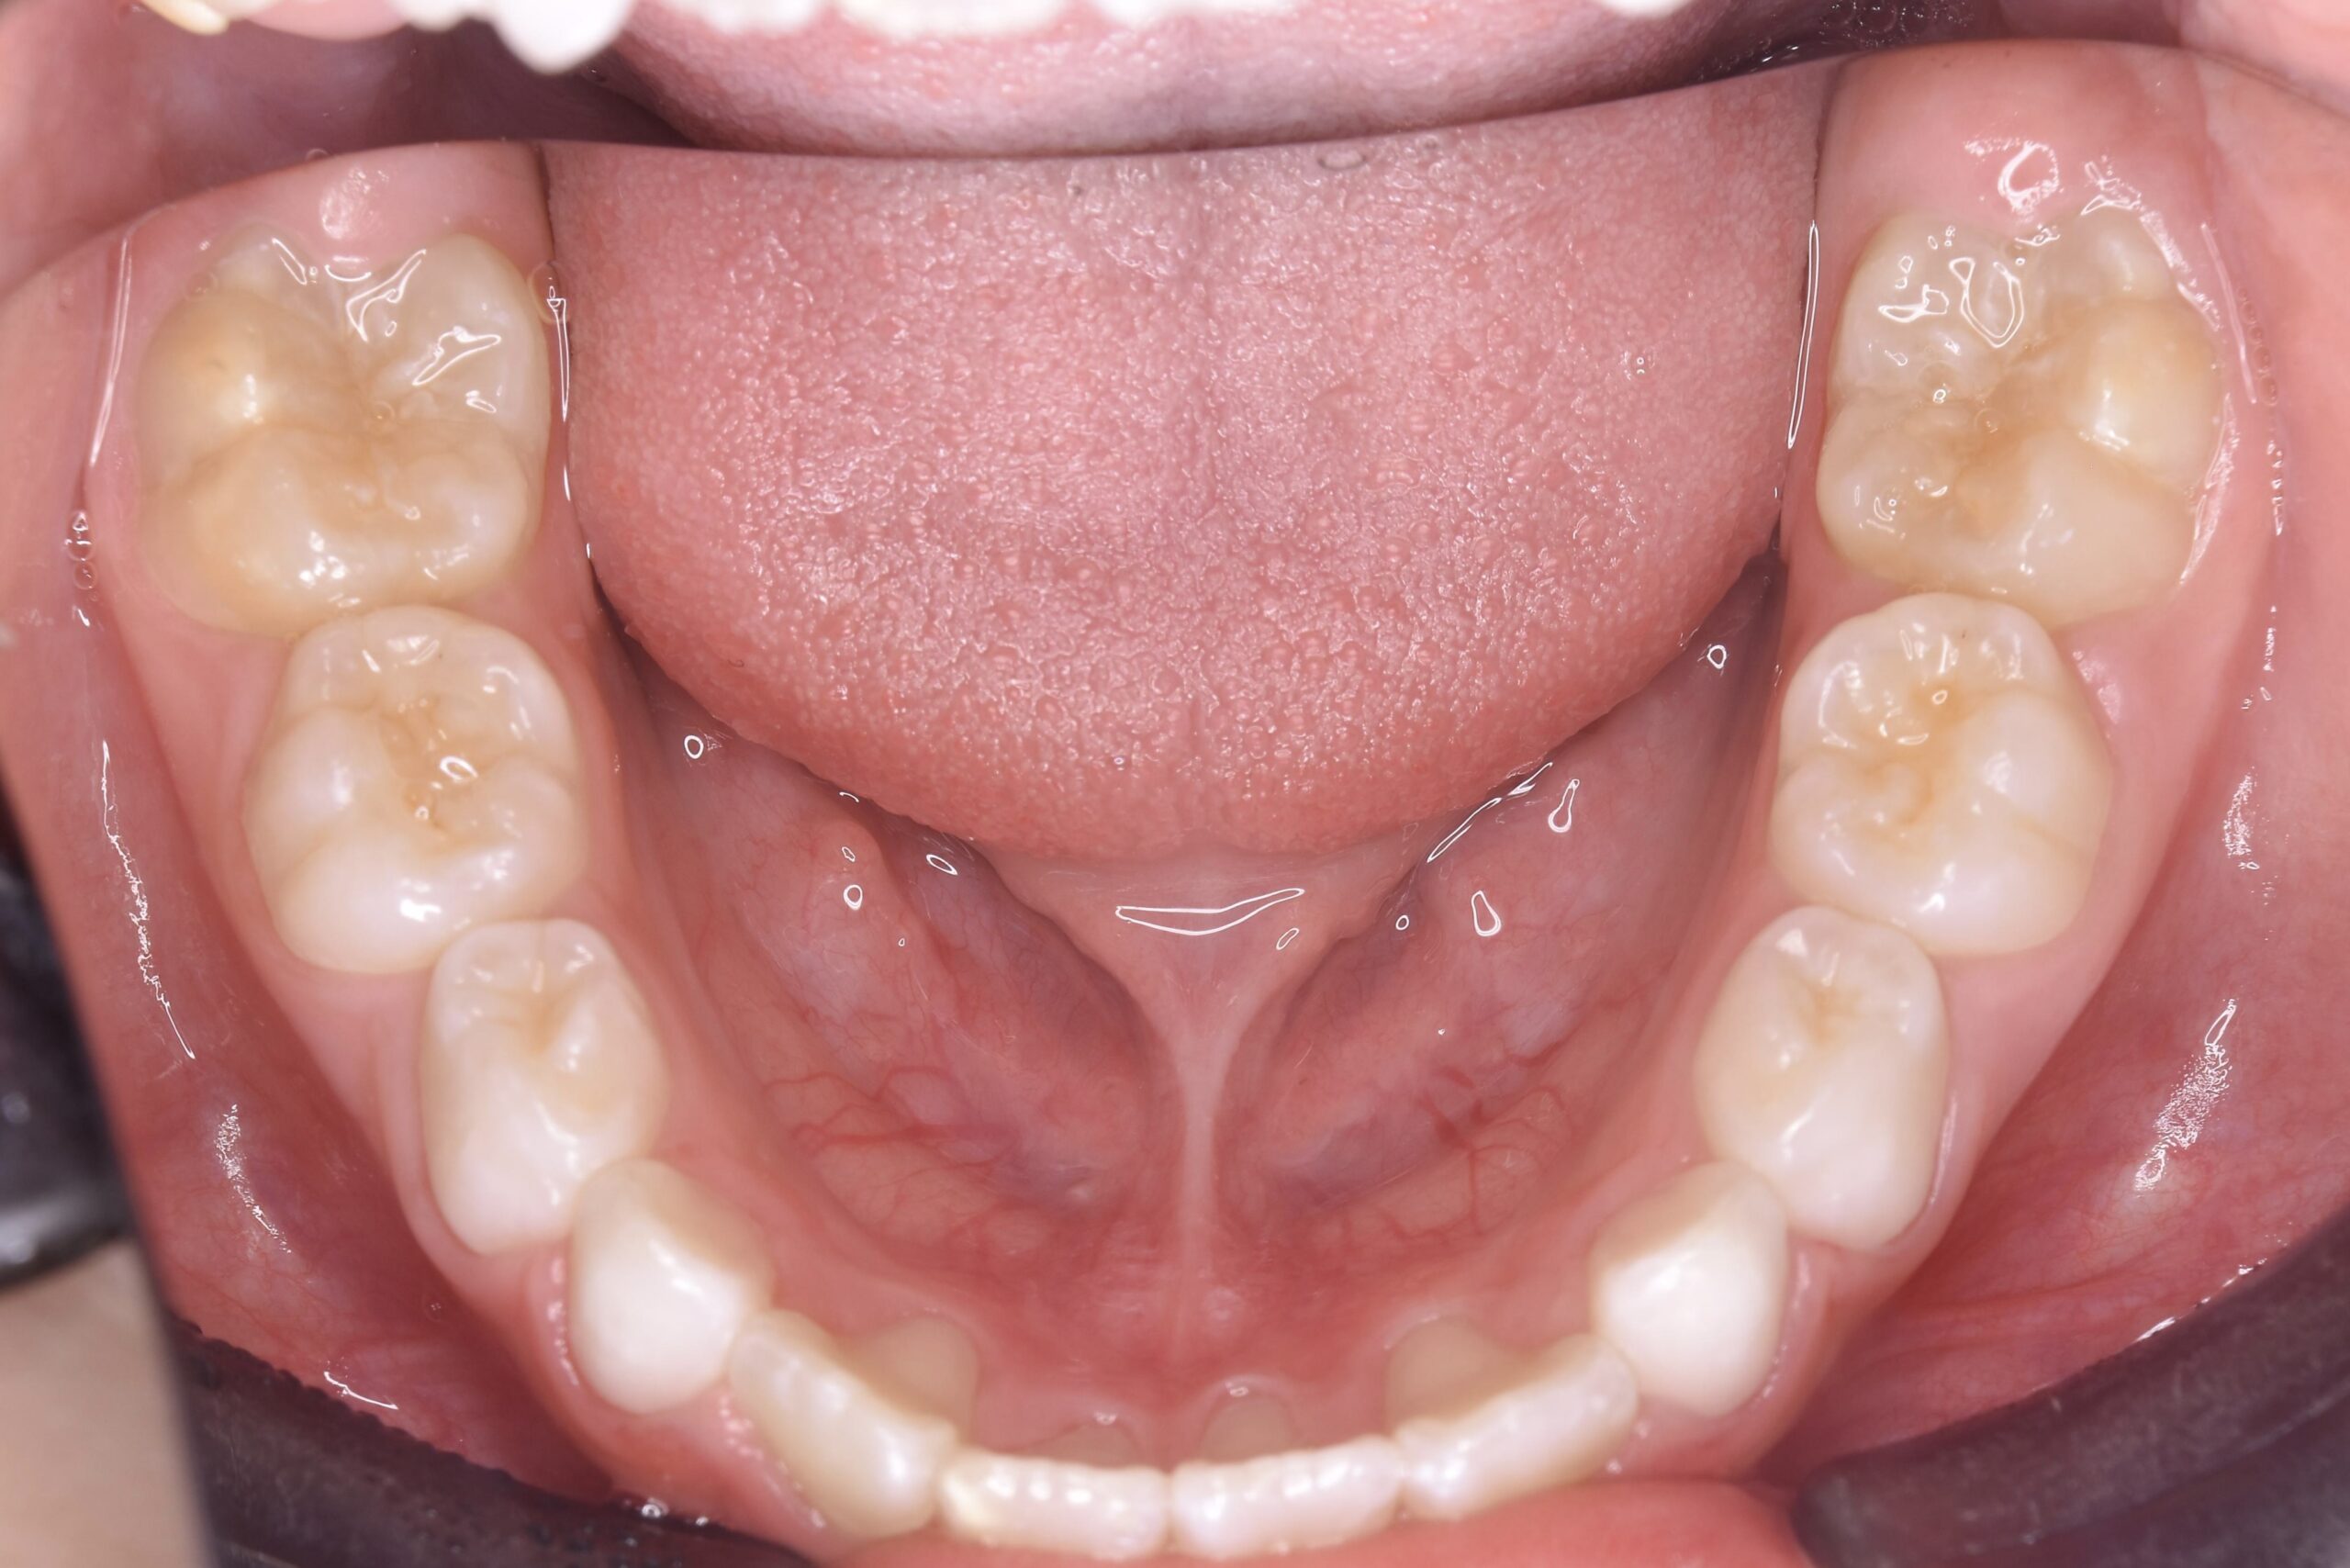

AFTER

治療内容

上下の歯並びの幅を拡げつつ、前歯の関係を改善しました。

使用装置

急速拡大装置

リンガルアーチ

機能的矯正装置(マイオブレース)

抜歯部位

抜歯なし

治療期間

2年 + 後戻り止め期間(5年)

通院回数

25回

費用

50万円程度(税別)